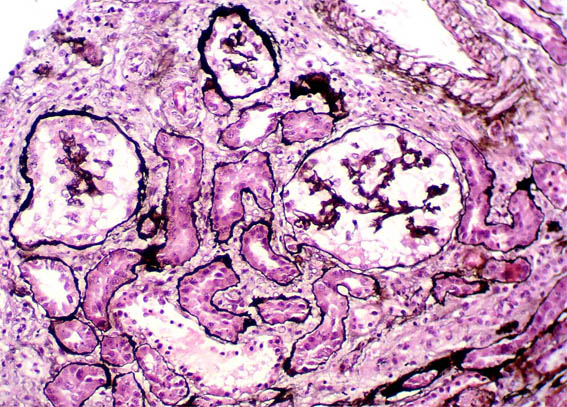

Figure 4. Methenamine-silver, X400.

Figure 5. Methenamine-silver, X200.